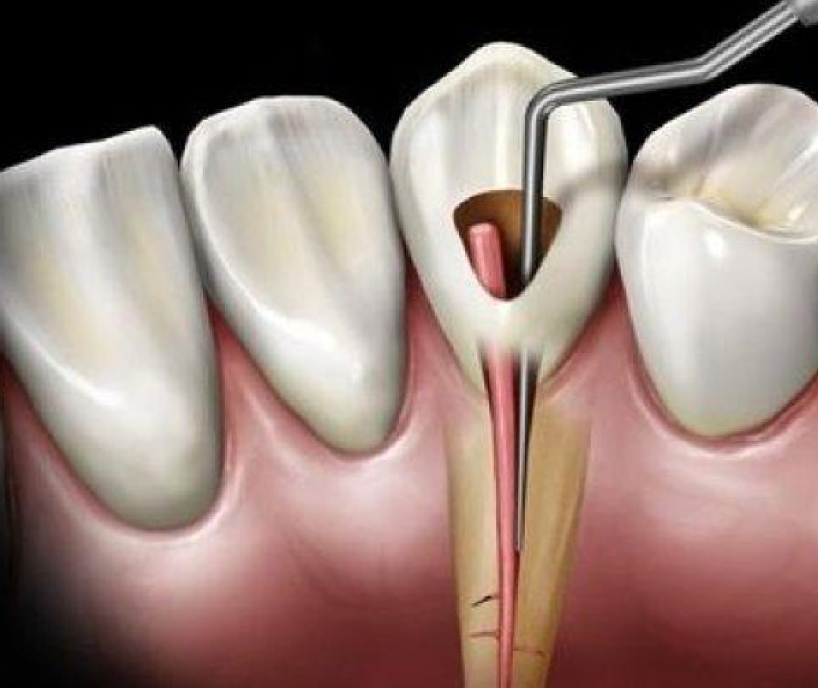

Conductores

El tratamiento de conducto es un procedimiento dental que busca remover las bacterias y el tejido nervioso que se encuentra muerto o en estado de descomposición del interior de una pieza dental. El objetivo de este procedimiento odontológico es «salvar» a un diente que se ha infectado o ha “muerto”, en un intento para que sea funcional y quede libre de dolor.

En CM manejamos diferentes tipo de conductores los cuales son:

-

Multiradicular

-

Biradicular